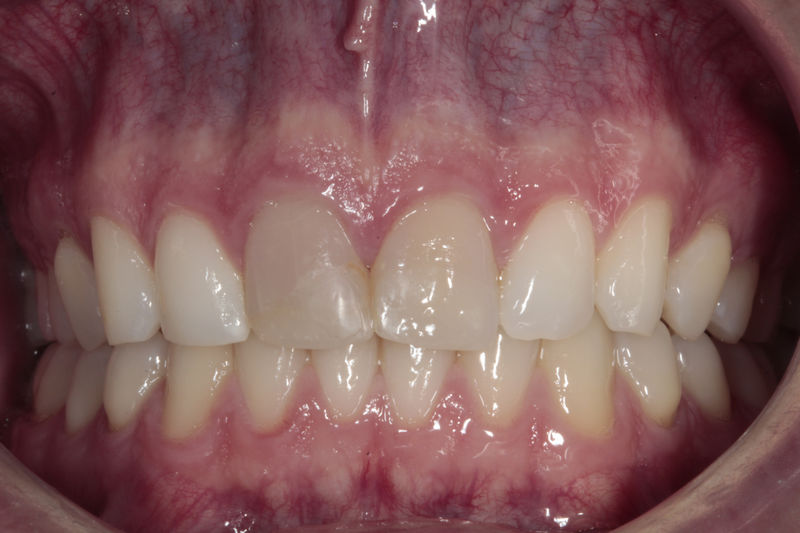

Implante fracasado, extracción, carillas, coronas y prótesis fija.